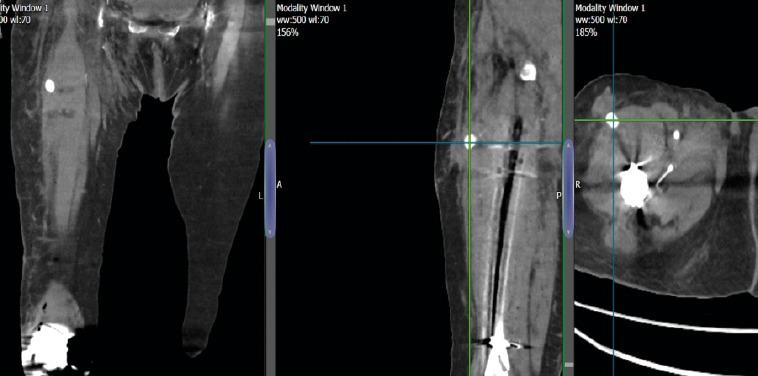

Retrograde femoral nailing is a frequently performed surgical procedure used to stabilize a supracondylar femur fracture. We are reporting a unique case where the insertion of the anteroposterior interlocking screw of a retrograde nail caused vascular damage. Within the elderly patient population, we anticipate the presence of significant collateral blood vessels, which increases the potential for vascular damage during the insertion of a proximal screw. In this instance, there was bleeding caused by a vascular injury after the insertion of proximal interlocking screws, which necessitated further examination and vascular embolization on the following day. The complexity above necessitates that the author makes adjustments to surgical techniques when inserting proximal screws of a retrograde nail in similar cases.

An 82-year-old female patient presented with a right periprosthetic supracondylar femur fracture. The fracture was managed by retrograde nail femur. Vascular injury during proximal anteroposterior screw insertion results in post-operative bleeding and marked hemoglobin drop. The bleeding is managed by computed tomography emergent vascular embolization.

1例82岁女性患者,因右股骨假体周围髁上骨折入院,采用逆行股骨交锁髓内钉固定。近端前后螺钉置入时发生血管损伤,导致术后出血及血红蛋白显著下降,通过CT引导下紧急血管栓塞治疗出血。